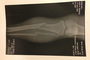

Es war ein unglücklicher Sturz, als Leon Haslam in Assen bereits im ersten Training von der Piste flog. Sein Bein kam zwischen Rad und Motorrad – der menschliche Knochen zog den Kürzeren. Das Schienbein wurde mit einem Marknagel fixiert.

Denn nicht nur Bruch muss verheilen, auch Bänder und Muskeln wurden beschädigt. «Es sind massive Verletzungen an Muskeln, einige Bänder wurde überdehnt», sagt der 29-Jährige, der bereits wieder zu Hause ist und beginnt, das Bein zu belasten.